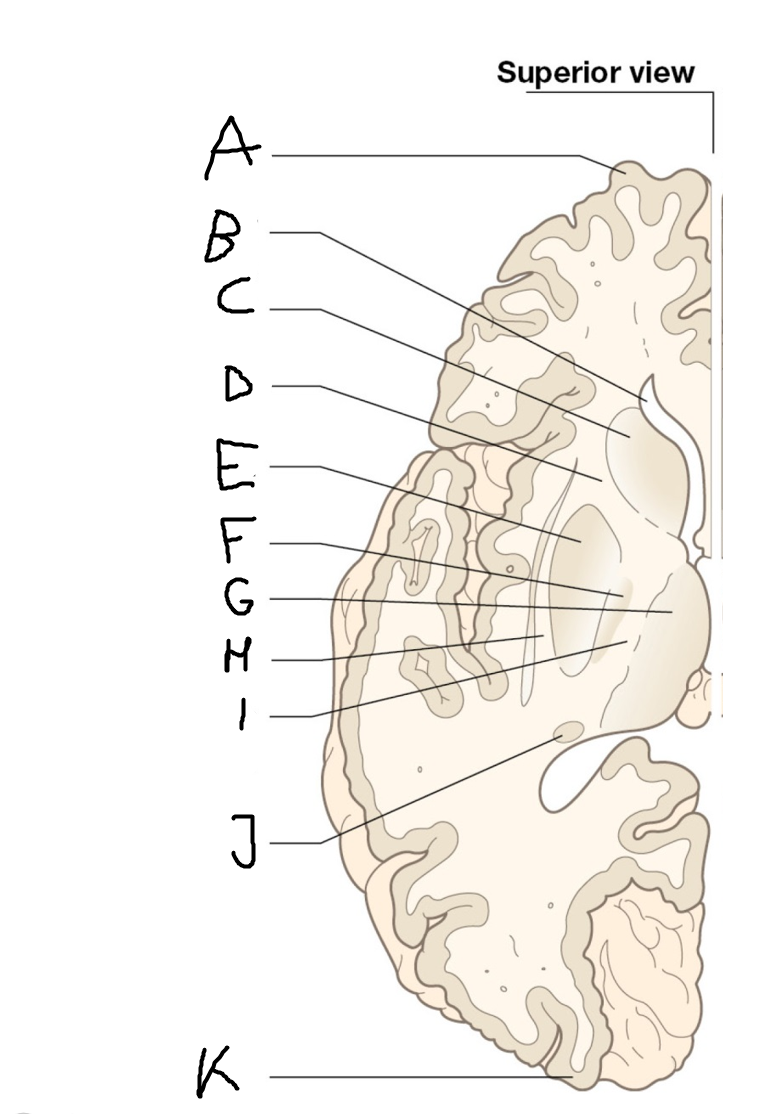

internal capsule (posterior limb)

B

anterior horn of lateral ventricle

C

head of caudate nucleus

D

internal capsule (anterior limb)

E

putamen

F

globus pallidus

G

Thalamus

H

External capsule

I

internal capsule (posterior limb)

J

tail of caudate nucleus